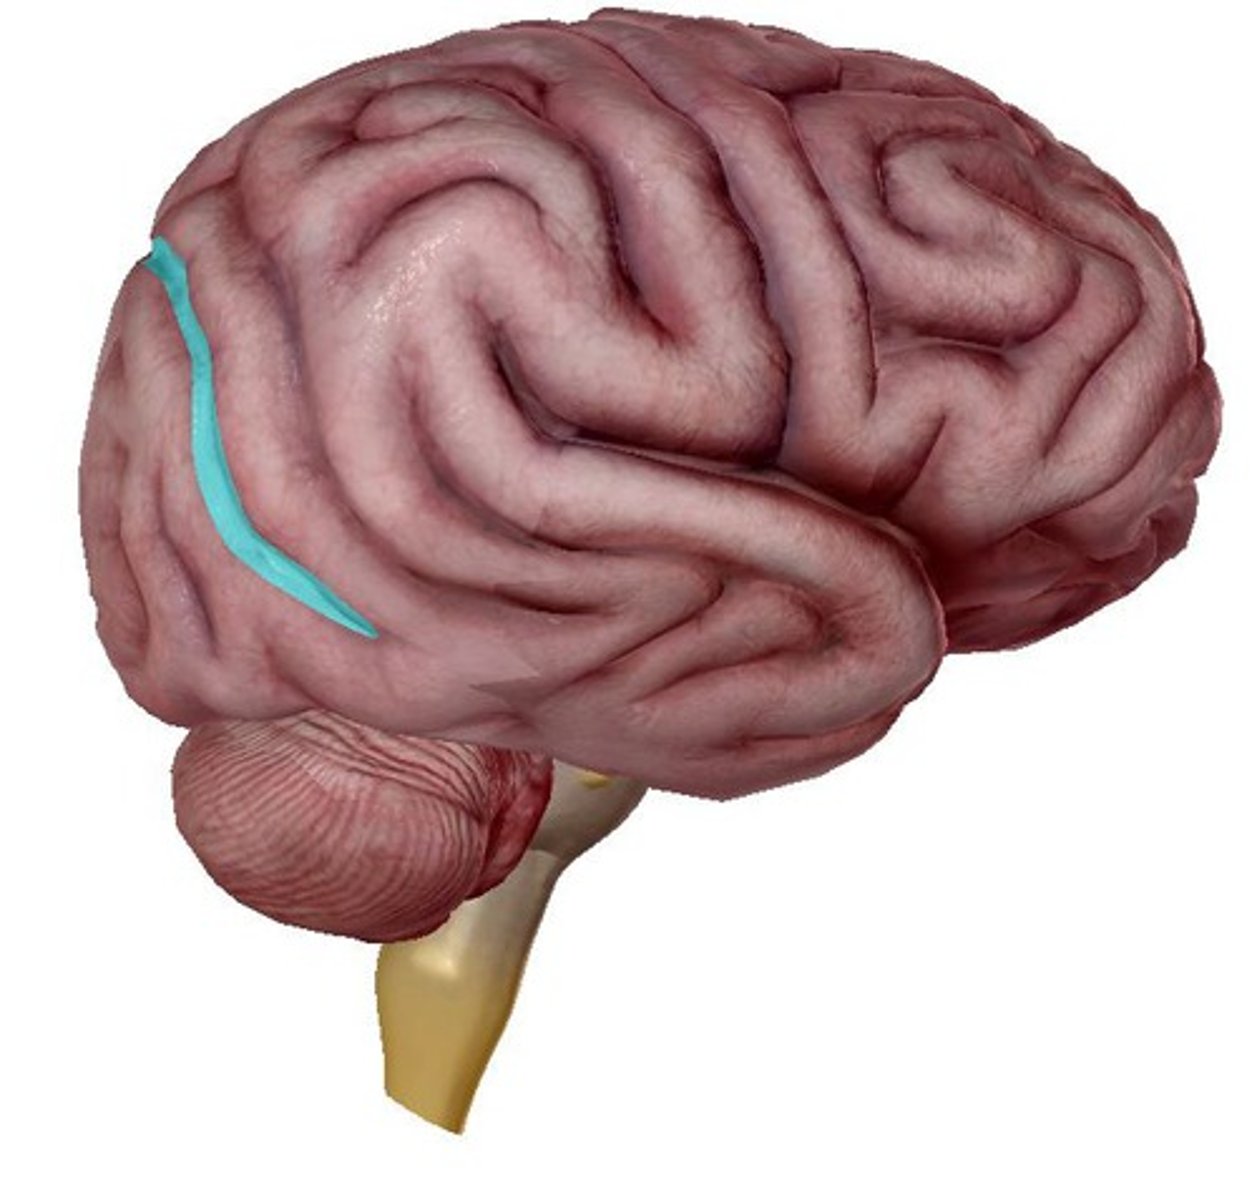

lateral fissure

central sulcus

precentral gyrus

postcentral gyrus